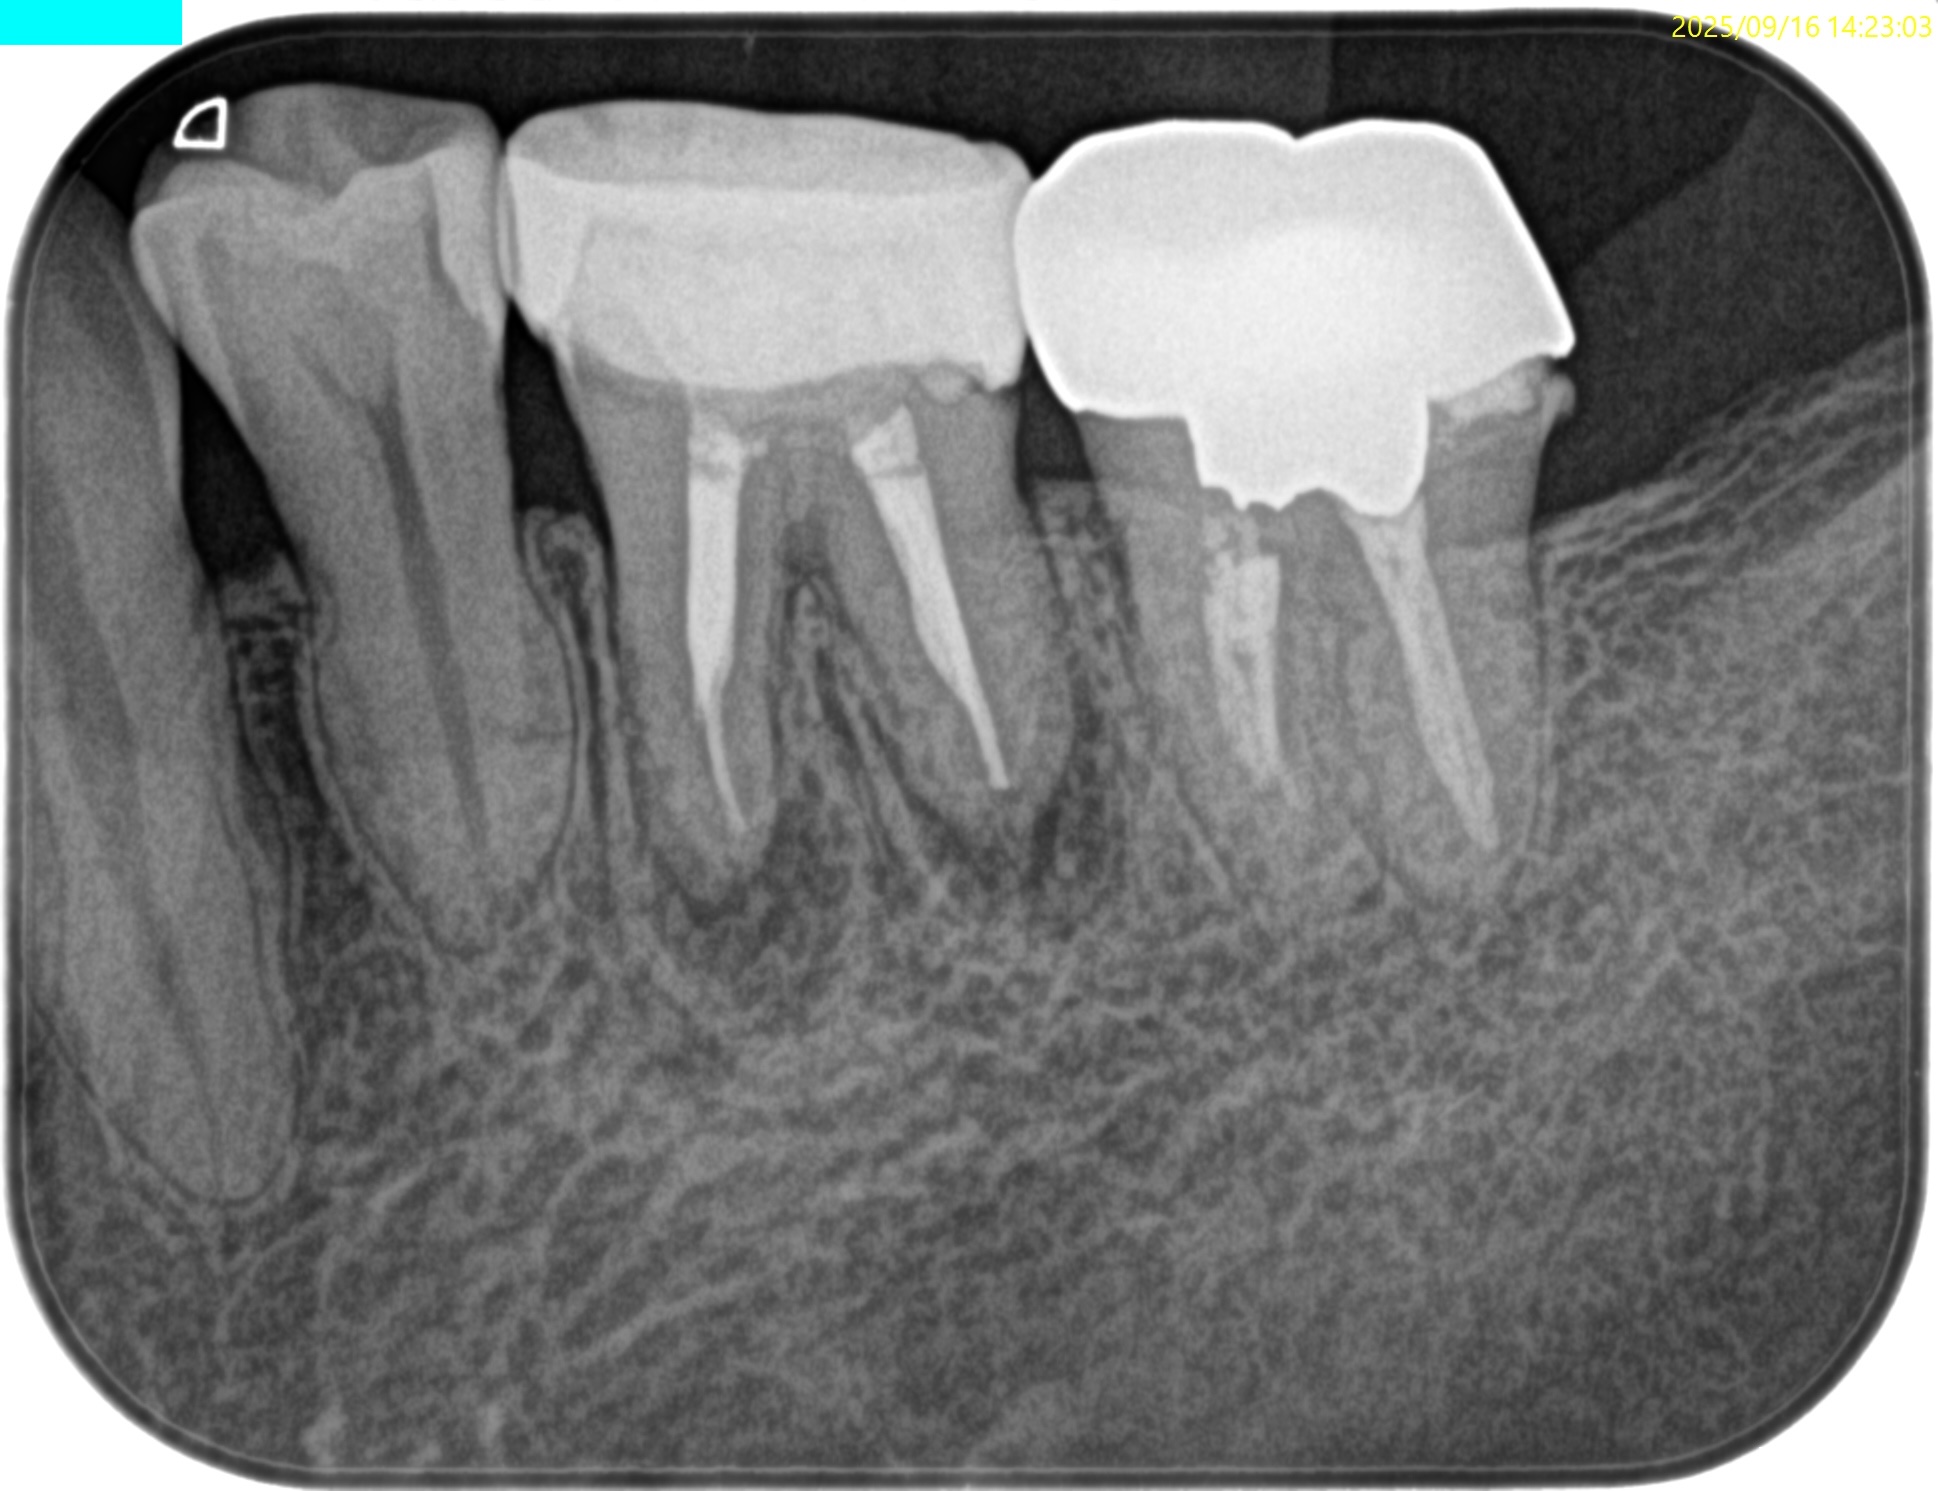

#19 Re-RCT(2025.10.6)

術後にPA, CBCTを撮影した。